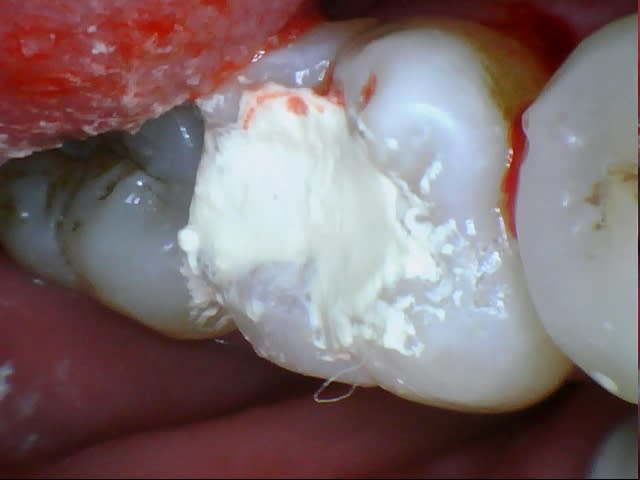

De belles cornes bien visibles, et c'était limite, ça saignait un peu, patient de 40 ans.

J'ai vu aujourd'hui à J+7 (dernière image), sensibilité modérée au froid, dureté d'un eugénate normal.